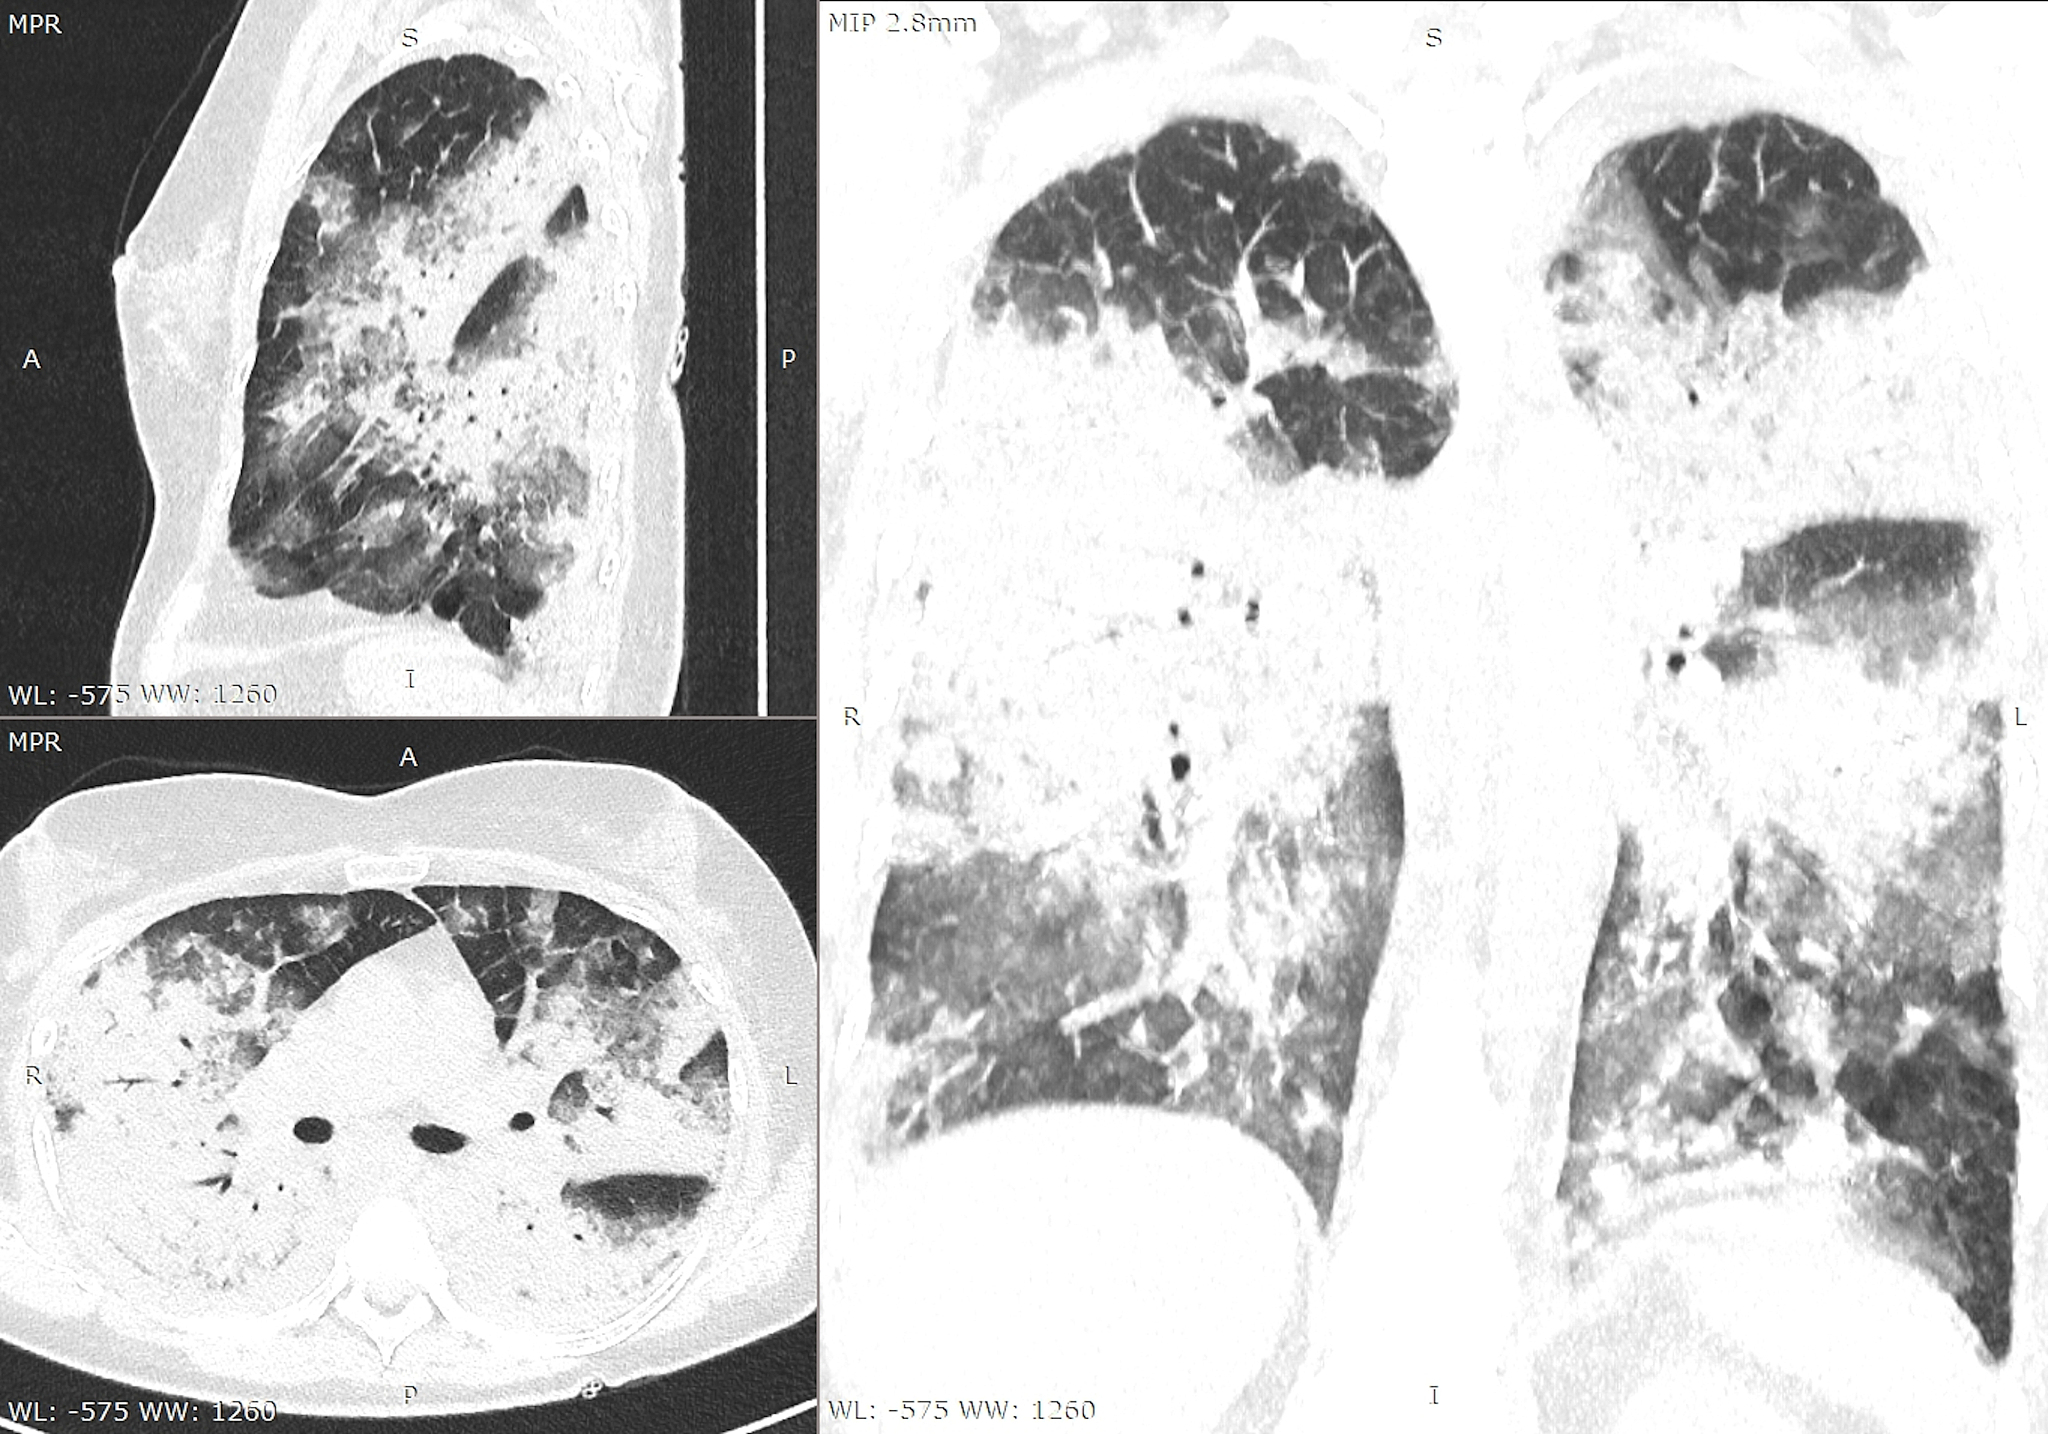

部位是指由多种不同组织构成的结构单元,具备特定的功能。根据对984份肺部CT报告及专利“一种影像诊断结果的结构化报告系统”的分析,肺部CT报告的“影像所见”部分可被分为六个部分:双肺区、气管支气管区、肾脏区、心脏区、胸膜区和胸廓区。这些部位并非实体,而是属性。

影像学报告的分析表明,准确限定病变发生的位置是非常重要的,而部位的确切描述能够确定相应疾病的存在。特定部位的出现与相应的影像学表现相结合,可以帮助医生做出正确的诊断。